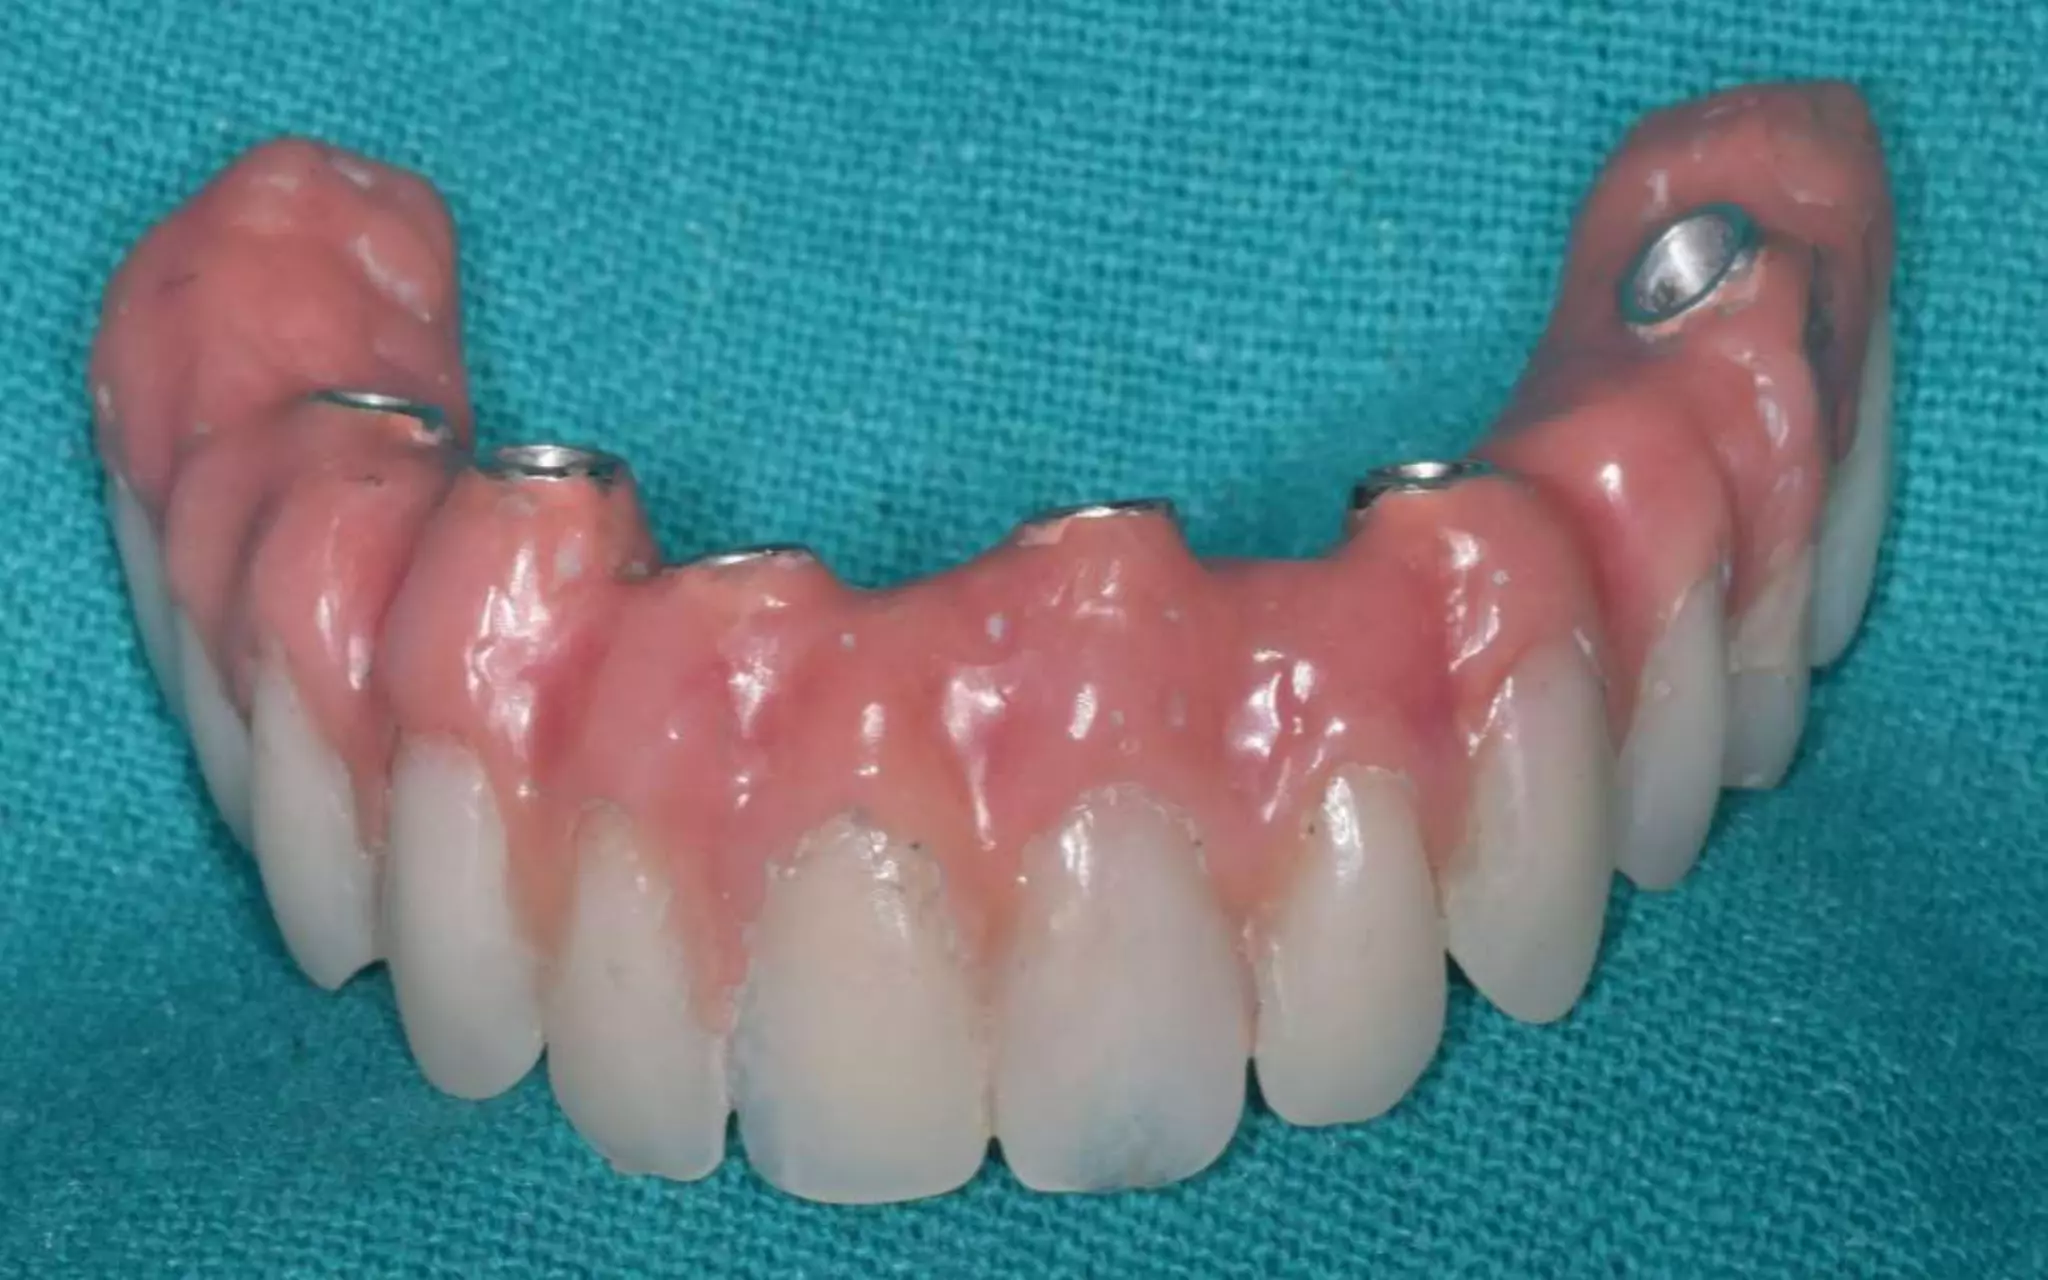

overdenture